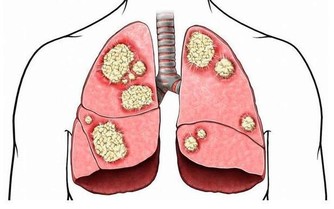

21. 癌症風險高

關於睡眠與癌症之間的關聯,

目前的研究仍在初期階段,不過就目前的結果來看,

睡眠不足確實會增加罹癌的風險,特別是大腸癌與乳癌。